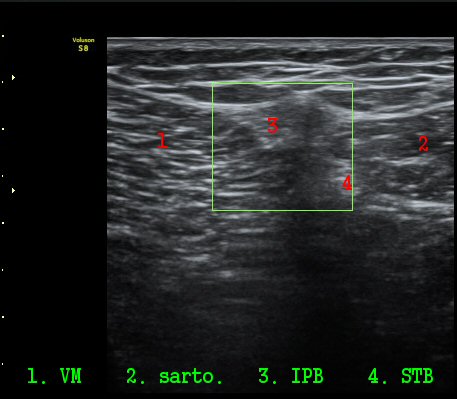

´ëÅð ³»Ãø, ¹«¸­ °üÀý¸é¿¡¼­ ¾à 10 cm ±ÙÀ§ºÎȾ´Ü¸é°Ë»ç¿¡¼­ ³»Ãø±¤±Ù°ú ºÀRHD±Ù(sartorius)

»çÀÌ¿¡¼­ º¹Àç½Å°æÀÌ °í¿¡ÄÚ Å¸¿øÇü ¾ç»óÀ¸·Î °í³ªÂûµÈ´Ù(»çÁø 2).

ŽÃËÀÚ¸¦ ¸»´ÜÀ¸·Î À̵¿ÇÏ´Ï º¹Àç½Å°æÀÌ ½½°³°ñÇϰ¡Áö¿Í  ºÀ°ø°¡Áö(sartorial branch)·Î

°¥¶óÁö´Â °ÍÀÌ °üÂûµÇ°í(»çÁø 3, 4, 5) µ¿¿µ»ó È­¸éÀ¸·Î º¸¸é ´õ¿í ¶Ñ·ÈÇÏ´Ù(÷ºÎ ÆÄÀÏ 1)

º¹Àç½Å°æ ½½°³°ñÇϰ¡Áö°¡ È®ÀÎµÈ »óÅ¿¡¼­ ´ëÅð ¾Õ¿¡¼­ ÃÊÀ½ÆÄÀ¯µµÇÏ ½½°³°ñÇϰ¡Áö

Â÷´ÜÀ» ½ÃÇàÇÏ¿´´Ù(÷ºÎ ÆÄÀÏ 2).